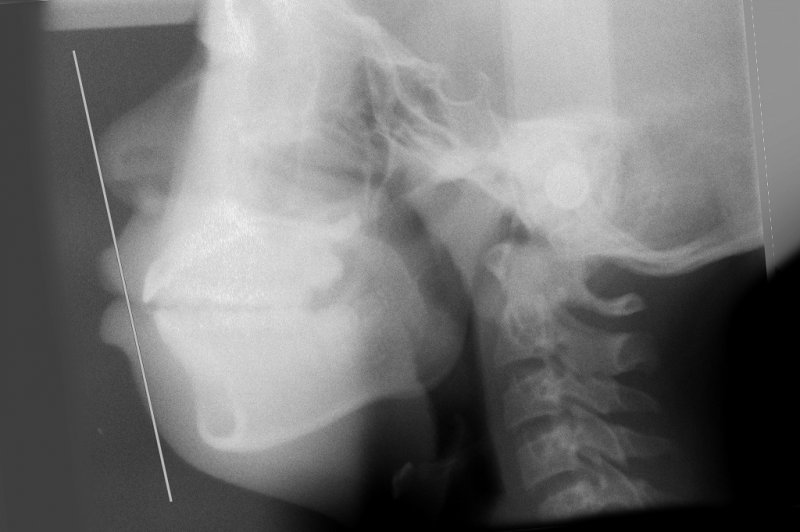

セファロ分析による客観的評価

矯正治療においては、主観的な印象だけでなく客観的な骨格評価が重要です。その際に用いられるのがセファログラム(頭部X線規格写真)です。

セファロ分析では以下のような項目を評価します。

・Eラインと口唇の位置関係

・SNA角、SNB角などの骨格的指標

・フェイシャルパターン(長顔型・短顔型・中顔型)

これらの数値的評価により、口元の突出や骨格バランスを客観的に判断できます。治療前にセファロ分析を行い、治療後の顔貌変化を予測することが重要です。